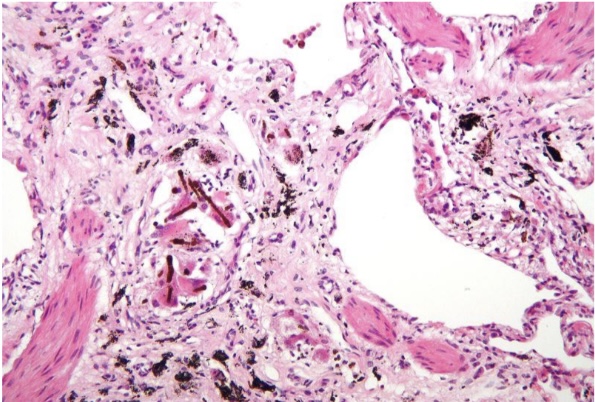

Anthracosis

Asbestosis

Chalicosis

Pneumoconiosis

Silicosis